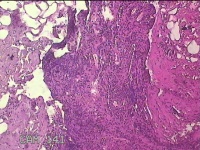

右侧耳垂结节

性别

男

年龄

24岁

临床诊断

耳垂新生物

一般病史

发现右侧耳垂结节3个月余。

标本名称

大体所见

灰白暗红色结节0.5x0.3x0.2cm一个,表面糜烂。

图2